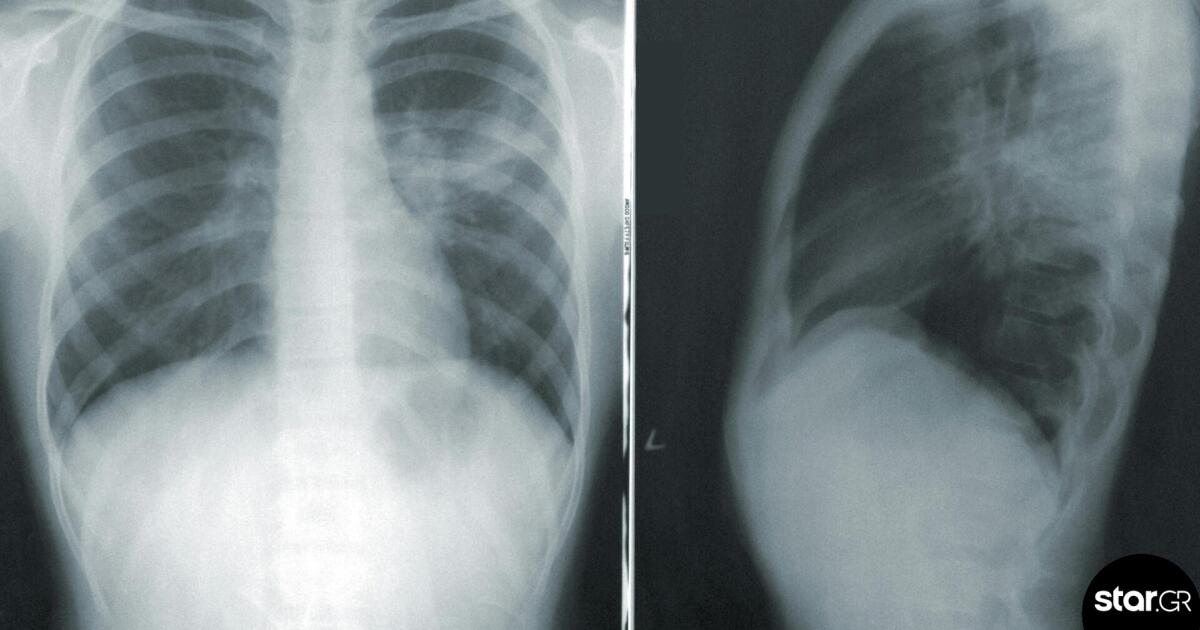

Οι πρόσφατες κλινικές δοκιμές είναι ενθαρρυντικές. Αν δουλέψει η τεχνική, θα μπορούσε να βοηθήσει τους γιατρούς να σώσουν ανθρώπους με πνευμονική δύσπνοια, έπειτα από τραυματισμό ή φλεγμονή ή με περιορισμένη αναπνευστική δυνατότητα λόγω κάποιας μεταδοτικής ασθένειας.

Το "Butt breathing" πρωτοπαρουσιάστηκε το 2021, όταν η επιστημονική ομάδα δοκίμασε την τεχνολογία σε χοίρους που δυσκολεύονταν να αναπνεύσουν μέσω των πνευμόνων τους. Τα επίπεδα οξυγόνου στα αιμοφόρα αγγεία των ζώων αυξήθηκαν ραγδαία, έπειτα την έγχυση ενός διαλύματος πλούσιου σε οξυγόνο. Τα αποτελέσματα έδειξαν ότι η αναπνευστική δυσφορία και δυσχέρεια των ζώων βελτιώθηκε υπό ορισμένες συνθήκες.

Πρόσφατα, η καινοτόμος αυτή μέθοδος δοκιμάστηκε και σε ανθρώπους, μέσω μίας έρευνας που διεξήχθη από Αμερικανούς και Ιάπωνες επιστήμονες σε 27 υγιείς άνδρες εθελοντές, ηλικίας 20 έως 45 χρόνων.